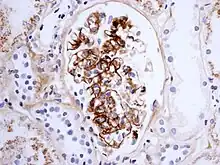

Morphology

Histologically, IgA nephropathy may show mesangial widening and focal and segmental inflammation. Diffuse mesangial proliferation or crescentic glomerulonephritis may also be present. Immunofluorescence shows mesangial deposition of IgA often with C3 and properdin and smaller amounts of other immunoglobulins (IgG or IgM). Early components of the classical complement pathway (C1q or C4) are usually not seen. Electron microscopy confirms electron-dense deposits in the mesangium that may extend to the subendothelial area of adjacent capillary walls in a small subset of cases, usually those with focal proliferation.

The disease derives its name from deposits of immunoglobulin A (IgA) in a granular pattern in the mesangium (by immunofluorescence), a region of the renal glomerulus. The mesangium by light microscopy may be hypercellular and show increased deposition of extracellular matrix proteins. In terms of the renal manifestation of Henoch–Schönlein purpura, it has been found that although it shares the same histological spectrum as IgA nephropathy, a greater frequency of severe lesions such as glomerular necrosis and crescents were observed. Correspondingly, HSP nephritis has a higher frequency of glomerular staining for fibrin compared with IgAN, but with an otherwise similar immunofluorescence profile.[4]